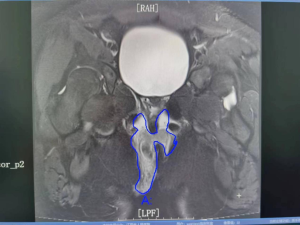

经详细问诊及专科检查,发现右侧肛周见8*6cm红肿范围,按之有波动感,小琪被确诊为“肛周脓肿”。针对小琪的情况,肛门肛肠外科副主任医师毛丽华建议入院并行急诊手术。在毛丽华团队的努力下,当天为小琪进行了肛周磁共振检查,并行急诊肛周脓肿根治术。术中引流出约150ml浓稠、腥臭味脓性分泌物,并妥善处理内口,因脓肿波及范围大,术中采用挂线术,极大限度的保护肛门括约肌。并将脓肿组织送病理,病理诊断为炎性肉芽组织,符合肛周脓肿诊断。术后予抗感染、止痛、清洁换药等对症治疗,8天后患者创面恢复尚可,予以办理出院,一个月后小琪肛旁创面已基本痊愈,重返校园。

诊断:临床表现(肛门肛周疼痛+发热)+肛门指检+检验(血常规)+检查(多见于MRI)。

当然本病的疼痛和发热表现也需要视病情而定,表浅的脓肿局部疼痛症状明显,全身发热症状可能不突出;深部的脓肿局部无明显表现,但容易引发高热,因此肛周磁共振能很好的提示脓肿的范围及位置。